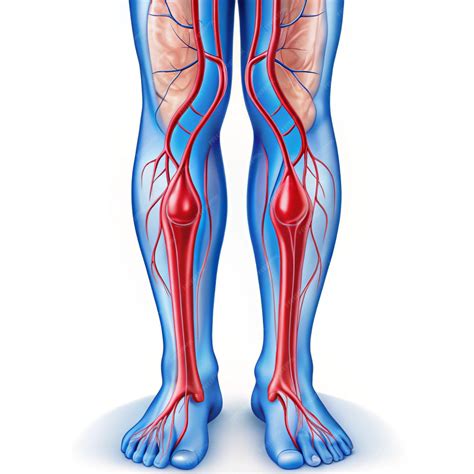

8. Insuficiencia Venosa Crónica

La insuficiencia venosa crónica (IVC) ocurre cuando la sangre no fluye adecuadamente desde las piernas hacia el corazón debido a válvulas dañadas. Esto provoca que la sangre se acumule en las venas de las pantorrillas, especialmente alrededor de los pies y tobillos, causando retención de líquidos. Los síntomas de la IVC incluyen piernas adoloridas, cambios en la piel (como descamación), aparición de nuevas venas varicosas, úlceras cutáneas e infecciones. Un diagnóstico y tratamiento tempranos son cruciales. El tratamiento puede incluir cambios en el estilo de vida (ejercicio, medias de compresión), medicamentos para prevenir coágulos sanguíneos y, en algunos casos, cirugía para reparar las válvulas dañadas.

9. Coágulos Sanguíneos (Trombosis Venosa Profunda)

Los coágulos sanguíneos se forman cuando la sangre no fluye correctamente y las plaquetas se agrupan. Si un coágulo se desarrolla en las venas de las piernas, puede impedir el retorno de la sangre al corazón, causando hinchazón en tobillos y pies. La trombosis venosa profunda (TVP) es una condición grave donde se forman coágulos en las piernas, pudiendo bloquear venas importantes. Los síntomas de TVP incluyen hinchazón en una pierna, dolor o molestia, fiebre baja y cambios en el color de la pierna. La TVP es una emergencia médica que requiere atención inmediata. El tratamiento principal es con medicamentos anticoagulantes. Las medidas preventivas incluyen el uso de medias de compresión, mantenerse activo y evitar estar de pie o sentado por períodos prolongados.